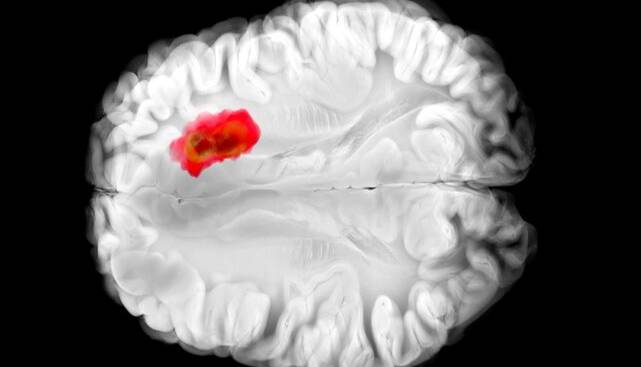

تصور میشود که همین آنزیم در سرطانهای مغزی گلیوبلاستومای تهاجمی نقش دارد. این درک جدید از «هیدرالازین» میتواند راه را برای درمانهای جدید سرطان هموار کند و همچنین اثربخشی دارو را برای اهداف فعلی آن بهبود بخشد.

مطالعات قبلی نشان دادهاند که تومورهای گلیوبلاستوما اغلب سرشار از ADO هستند و آن را برای تولید ماده شیمیایی به نام هیپوتائورین(hypotaurine) میربایند که به سلولهای سرطانی کمک میکند تا گسترش یابند، برای مدت طولانیتری زنده بمانند و فشار را تحمل کنند.

در آزمایشهایی که با سلولهای گلیوبلاستومای انسانی انجام شد، «هیدرالازین» با مسدود کردن ADO رشد تومور را متوقف کرد.